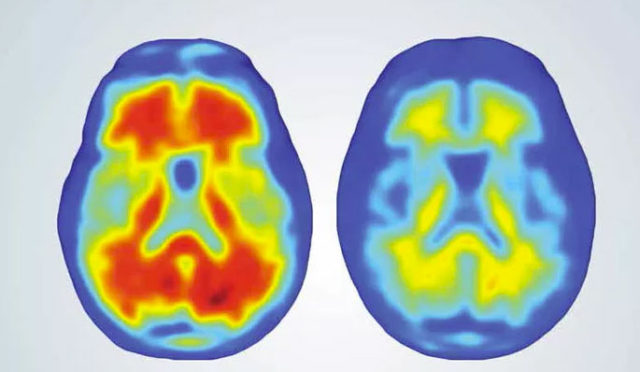

Uma nova e promissora terapia contra a doença de Alzheimer aparentemente consegue reduzir a característica acumulação de placas no cérebro dos pacientes, retardando a taxa de declínio mental que acompanha a doença.

Ao longo de um ano, a substância causou a retração das placas no cérebro e, mais importante, desacelerou a degeneração cognitiva que acompanha a doença. Os anticorpos visam seletivamente no cérebro a proteína beta-amiloide (A-beta), que forma as placas neurotóxicas, liga-se a ela e reduz suas formas solúveis e insolúveis.